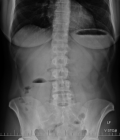

Diagnostic assessment: i) X-ray: plain abdominal radiography demonstrated small bowel air-fluid levels predominantly in the right mesogastric region, without pneumoperitoneum (Figure 1); ii) computed tomography (CT) scan: contrast-enhanced CT confirmed small bowel obstruction due to an internal hernia, with features suggestive of a right paraduodenal hernia (Figure 2-5); iii) laboratory tests: laboratory tests showed leukocytosis with a white blood cell (WBC) count of 12,400/mm3, while liver and kidney function tests, pancreatic enzymes, ionogram, C-reactive protein (CRP), and coagulation profile were all normal.

Figure 1: plain abdominal radiography demonstrated a small bowel air-fluid levels predominantly localized to the right mesogastric region, without evidence of pneumoperitoneum